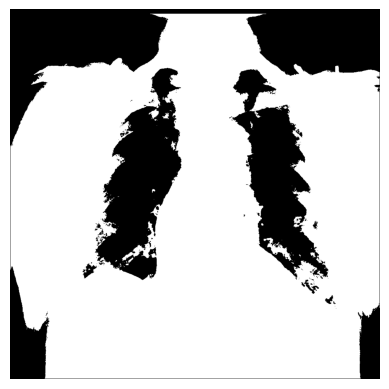

3. 您可以使用NumPy的np.where()创建不同的条件掩码 — 例如,只保留那些像素值超过特定阈值的图像部分。

# The threshold is "greater than 150"

# Return the original image if true, `0` otherwise

xray_image_mask_noisy = np.where(xray_image > 150, xray_image, 0)

plt.imshow(xray_image_mask_noisy, cmap="gray")

plt.axis("off")

plt.show()

# Return `1` if true, `0` otherwise

xray_image_mask_less_noisy = np.where(xray_image > 150, 1, 0)

plt.imshow(xray_image_mask_less_noisy, cmap="gray")